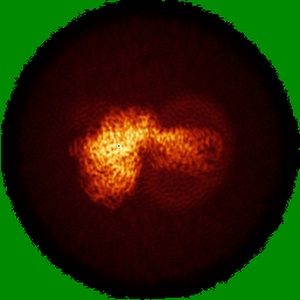

Cryo-EM structure of the ZH8667-bound mTAAR1-Gs complex

Single-particle3.1 Å